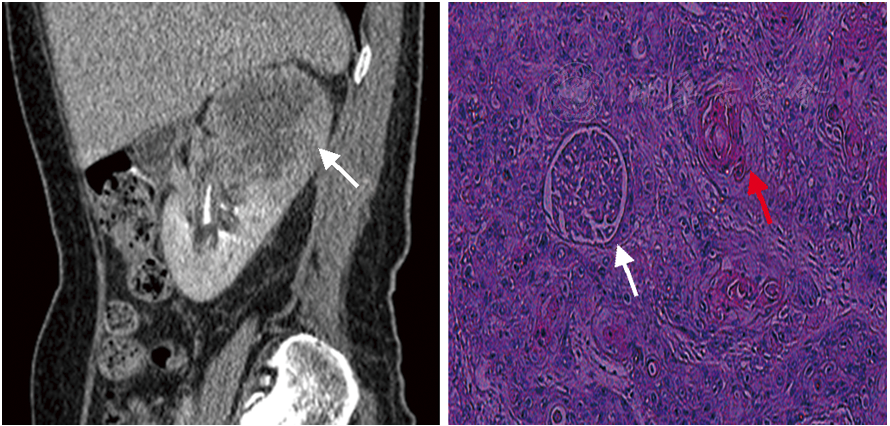

示右肾体积增大,右肾上极示不规则团块状稍低密度影,大小约7 cm×6 cm×5 cm,病灶边界不清,右肾周围脂肪间隙尚清;增强扫描病灶呈边缘轻度延迟强化,强化程度较正常肾实质低,中央部分未见明显强化;肾门区、腹膜后、下腔静脉前方示增大淋巴结影(图1)。

全麻下行右肾切除术,术中见右肾体积增大,与肾周组织无明显粘连。大体标本:见完整肾脏,大小约12 cm×8 cm×6 cm,右肾上极见一肿物,大小约7 cm×6 cm×5 cm,切面灰白,质硬,界不清,累及肾被膜,肾门处见灰白色结节数枚,直径0.6~1.0 cm。病理诊断:右肾鳞状细胞癌(高-中分化),伴大片坏死,侵犯肾被膜及肾髓质,未累及肾周脂肪,输尿管及脉管断端均未见累及,肾门淋巴结3/7枚见转移(图2)。术后3个月行PET-CT检查提示两肺、腹腔及腹膜后多发转移表现。

图1.患者CT检查右肾矢状位重建图像,右肾上极肿块影,呈不均匀强化(白色箭头所示)

图2.肾鳞状细胞癌病理图,镜下示肾小球(白色箭头所示)周围大量肿瘤细胞浸润,并见角化株(红色箭头所示)(HE ×100)